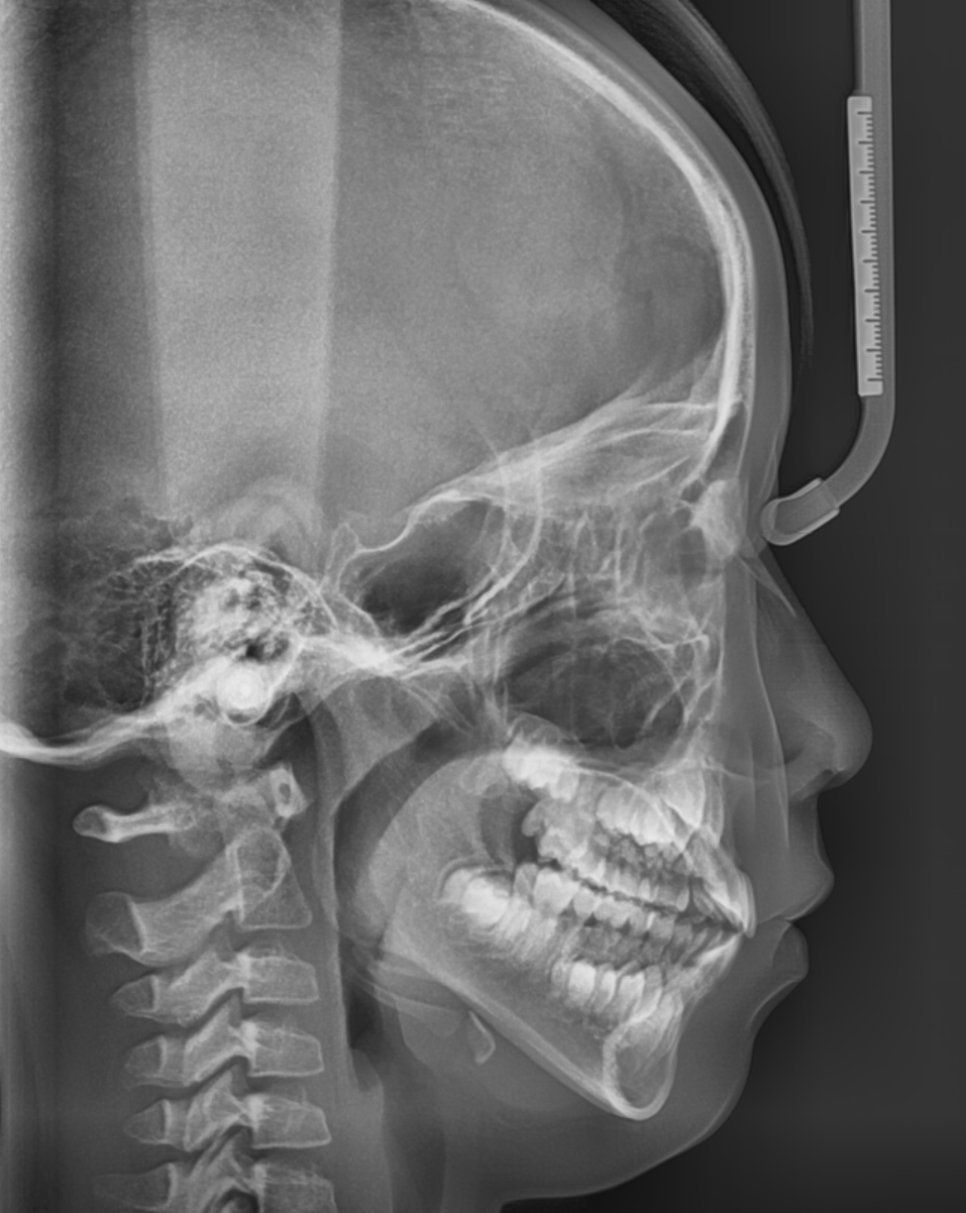

어린이 주걱턱이나 무턱일 경우

악궁 확장장치를 사용할 수도 있고

턱 뼈 성장까지 조절해야하기 때문에

초등학교 고학년 이전에 시작하여 끝내야합니다.

가장 적절한 시기는...

6세 전후로 첫 영구치가 나오기 때문에

이때쯤 치과 검진을 받아보시는 것을 추천드립니다.

어린이 치아 교정의 골든타임은 6~12세 입니다.